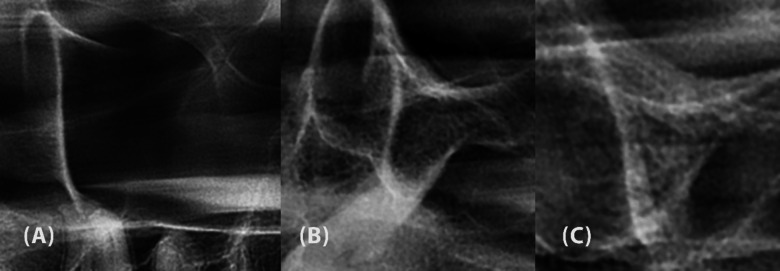

Recognizing the characteristics of the zygomatic process of the maxilla (ZPM) has several applications in implant dentistry and orthodontics. The present study evaluated the relationship between ZPM morphology, as obtained from panoramic images, and sinus pneumatization within the ZPM, according to cone-beam computed tomography (CBCT). CBCT and panoramic images of 300 patients were obtained, and the patients were divided into three age groups: Group I (15-34 years), Group II (35-55 years), and Group III (≥ 55 years). ZPM morphology was classified into J-shaped and non-J-shaped types based on panoramic images. The ZPM volume, maxillary sinus volume, and extent of sinus pneumatization within the ZPM were measured using CBCT scans, and their relationship to ZPM morphology classification was evaluated. Statistical analyses were performed using the Shapiro-Wilk test, one-way ANOVA, independent sample t-test, Mann-Whitney U test, Kruskal-Wallis test, and chi-square test (α = 0.05). Participants ranged in age from 17 to 82 years, and 67% were female. Most ZPMs were J-shaped (75%). J-shaped ZPMs had significantly greater sinus volume (1.83 ± 0.81 cm3), sinus pneumatization (53.56 ± 12.60%), and ZPM volume (3.50 ± 0.98 cm3) compared to non-J-shaped ZPMs (P < 0.05). Male participants had significantly larger ZPM volumes than females (P = 0.039). Sinus pneumatization and maxillary sinus volume were comparable across age groups and between gender. The presence of a non-J-shaped ZPM might be associated with less sinus pneumatization than J-shaped ZPMs, regardless of the patient's age or gender. Therefore, non-J-shaped ZPMs might offer more bone availability for various applications in dentistry.

Abstract Image